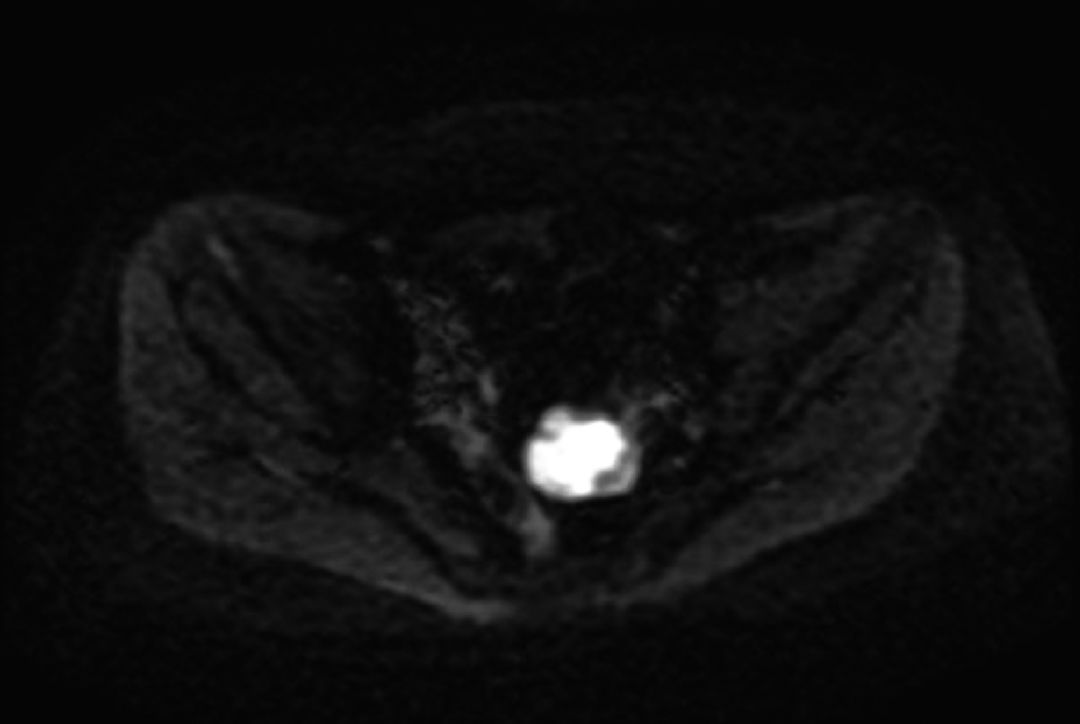

因“卵巢癌术后3 年余,下腹坠涨伴乏力半年余”于2016 年9 月初就诊于某三甲医院。患者于3 年前于外院行卵巢癌根治术,术后病检结果证实为卵巢来源子宫内膜样腺癌,术后予以紫杉醇+顺铂方案化疗8 个周期,化疗期间定期复查未见肿瘤复发及远处转移。近半年来,患者自觉下腹坠涨,久坐或排大便时自觉坠涨感加强就诊,胸部CT 检查未见异常(图1)。上腹部及盆腔MRI 检查(图2、图3):肝脏多发占位、腹壁异常占位及盆腔直肠区域异常占位,结合病史考虑患者为卵巢癌术后盆腔复发侵犯直肠,同时并肝脏多发转移。余影像检查无明显异常。

图2 上腹部MRI检查结果

图3 盆腔MRI检查结果